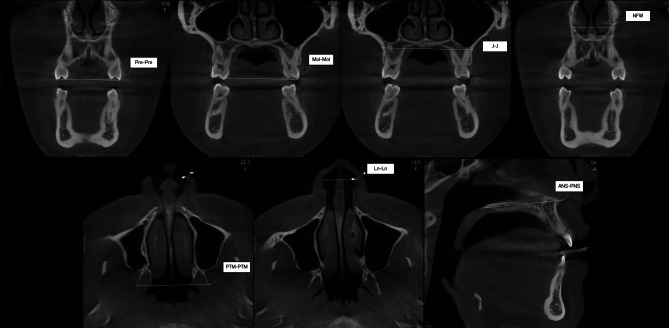

Materials and methods: Maxillary and mandibular tomographic examinations from 100 patients were analyzed to investigate the inter-premolar width, inter-molar width, maxillary width, inter-pterygoid width, nasal cavity width, nostril width, and maxillary length, obtained through Cone Beam Computed Tomography scans. The following machine learning algorithms were used to build the predictive models: Logistic Regression, Gradient Boosting Classifier, K-Nearest Neighbors (KNN), Support Vector Machine (SVM), Multi-Layer Perceptron Classifier (MLP), Decision Tree, and Random Forest Classifier. A 10-fold cross-validation approach was adopted to validate each model. Metrics such as area under the curve (AUC), accuracy, recall, precision, and F1 Score were calculated for each model, and Receiver Operating Characteristic (ROC) curves were constructed.